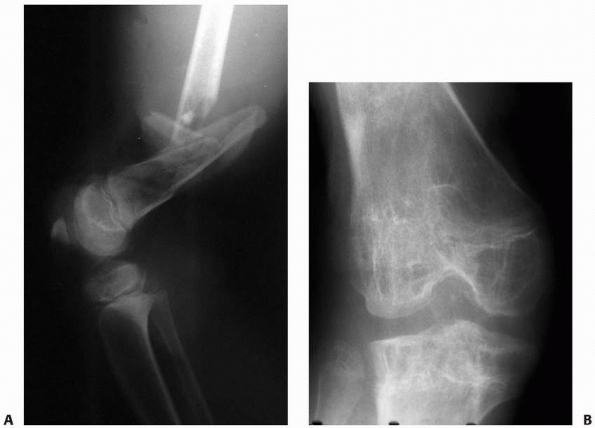

| Figure 5-8 Physeal injury from presumed vascular insult. A. The patient’s leg was caught under heavy pipes rolling off a rack, resulting in stripping of the soft tissues from the distal thigh, open comminuted fracture of the distal femur, and popliteal artery injury. B. In follow-up, after arterial and soft tissue reconstruction, the patient has physeal growth arrests of the distal femur and proximal tibia. The mechanism of injury to the proximal tibial physis was presumed to be vascular because of the associated femoral artery injury. |